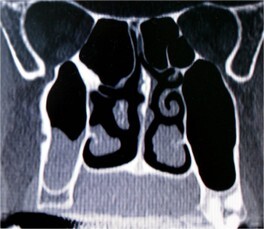

Il seno mascellare è uno dei quattro seni paranasali (seno sfenoidale, etmoidale, frontale e, appunto, mascellare) ed è morfologicamente il più voluminoso. I seni mascellari sono cavità situate all'interno delle ossa del cranio, sono rivestiti da mucosa respiratoria e comunicano tramite orifizi (chiamati osti) con le due cavità nasali. La perdita degli elementi dentali nel settore latero-posteriore dell’arcata superiore comporta un’atrofia dell’osso crestale e una lenta espansione della cavità sinusale. La richiesta del paziente di ripristinare in modo fisso i denti mancanti si scontra spesso con un ridotto o scarso volume osseo che rende necessaria la procedura chirurgica di rialzo del seno mascellare. In questi casi, infatti, non è possibile inserire in modo tradizionale gli impianti e si ha bisogno di volumi ossei più adeguati affinché gli impianti che vengono inseriti abbiano una lunghezza e un diametro sufficienti. Il termine "rialzo di seno" è dovuto proprio al fatto che i seni mascellari vengono spostati in alto dal ripristino dei volumi ossei, con materiali osteoconduttori, in modo da permettere un ancoraggio stabile degli impianti. Il posizionamento degli impianti è solitamente effettuato nell’ambito dello stesso intervento di rialzo del seno mascellare, in modo tale da ridurre il tempo globale di cura e protesizzazione. Il rialzo del seno mascellare si può eseguire con due tecniche: laterale o crestale. Con la prima tecnica si accede alla cavità del seno aprendo una piccola “finestra” ossea laterale procedendo cosi’ con visione diretta al riempimento della parte inferiore del seno mascellare. Nel rialzo del seno mascellare per via crestale invece si opera il rialzo del seno e il suo riempimento attraverso una piccola osteotomia crestale accedendo direttamente al seno a partire dalla cavità orale. Quest’ultima tecnica è sicuramente meno invasiva rispetto alla prima e il decorso post-operatorio è normalmente molto più rapido. Al fine di ridurre sempre piu’ l’invasività dell’atto chirurgico, in caso di osso crestale residuo di circa 5-6 mm, oggi e’ anche possibile ricorrere all’utilizzo di impianti corti che rappresentano una valida e predicibile alternativa al rialzo del seno mascellare.